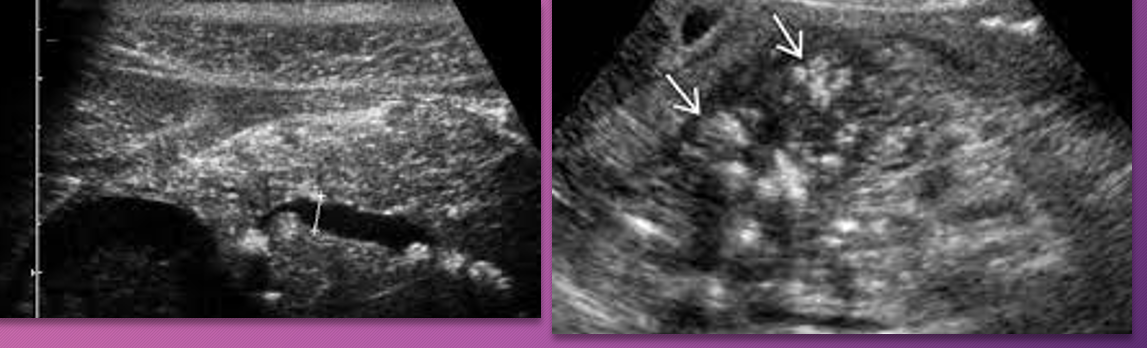

In the early stages of _____ pancreatitis, the sonographic appearance of the gland may _____ show _______ on sonography.

acute; NOT; swelling

When swelling does occur in acute pancreatitis, the sonographic appearance of the gland becomes ______ to _____ and is less _____ than the ______

hypoechoic; anechoic; echogenic; liver

When _____ does occur in _____ pancreatitis, the sonographic appearance of the gland becomes hypoechoic to anechoic and is less echogenic than the liver

Swelling; acute

_____ pancreatitis will have somewhat ______ but ________ borders, sonographically.

Acute; indistinct; smooth

Acute pancreatitis will have somewhat indistinct but smooth ______, sonographically

Borders